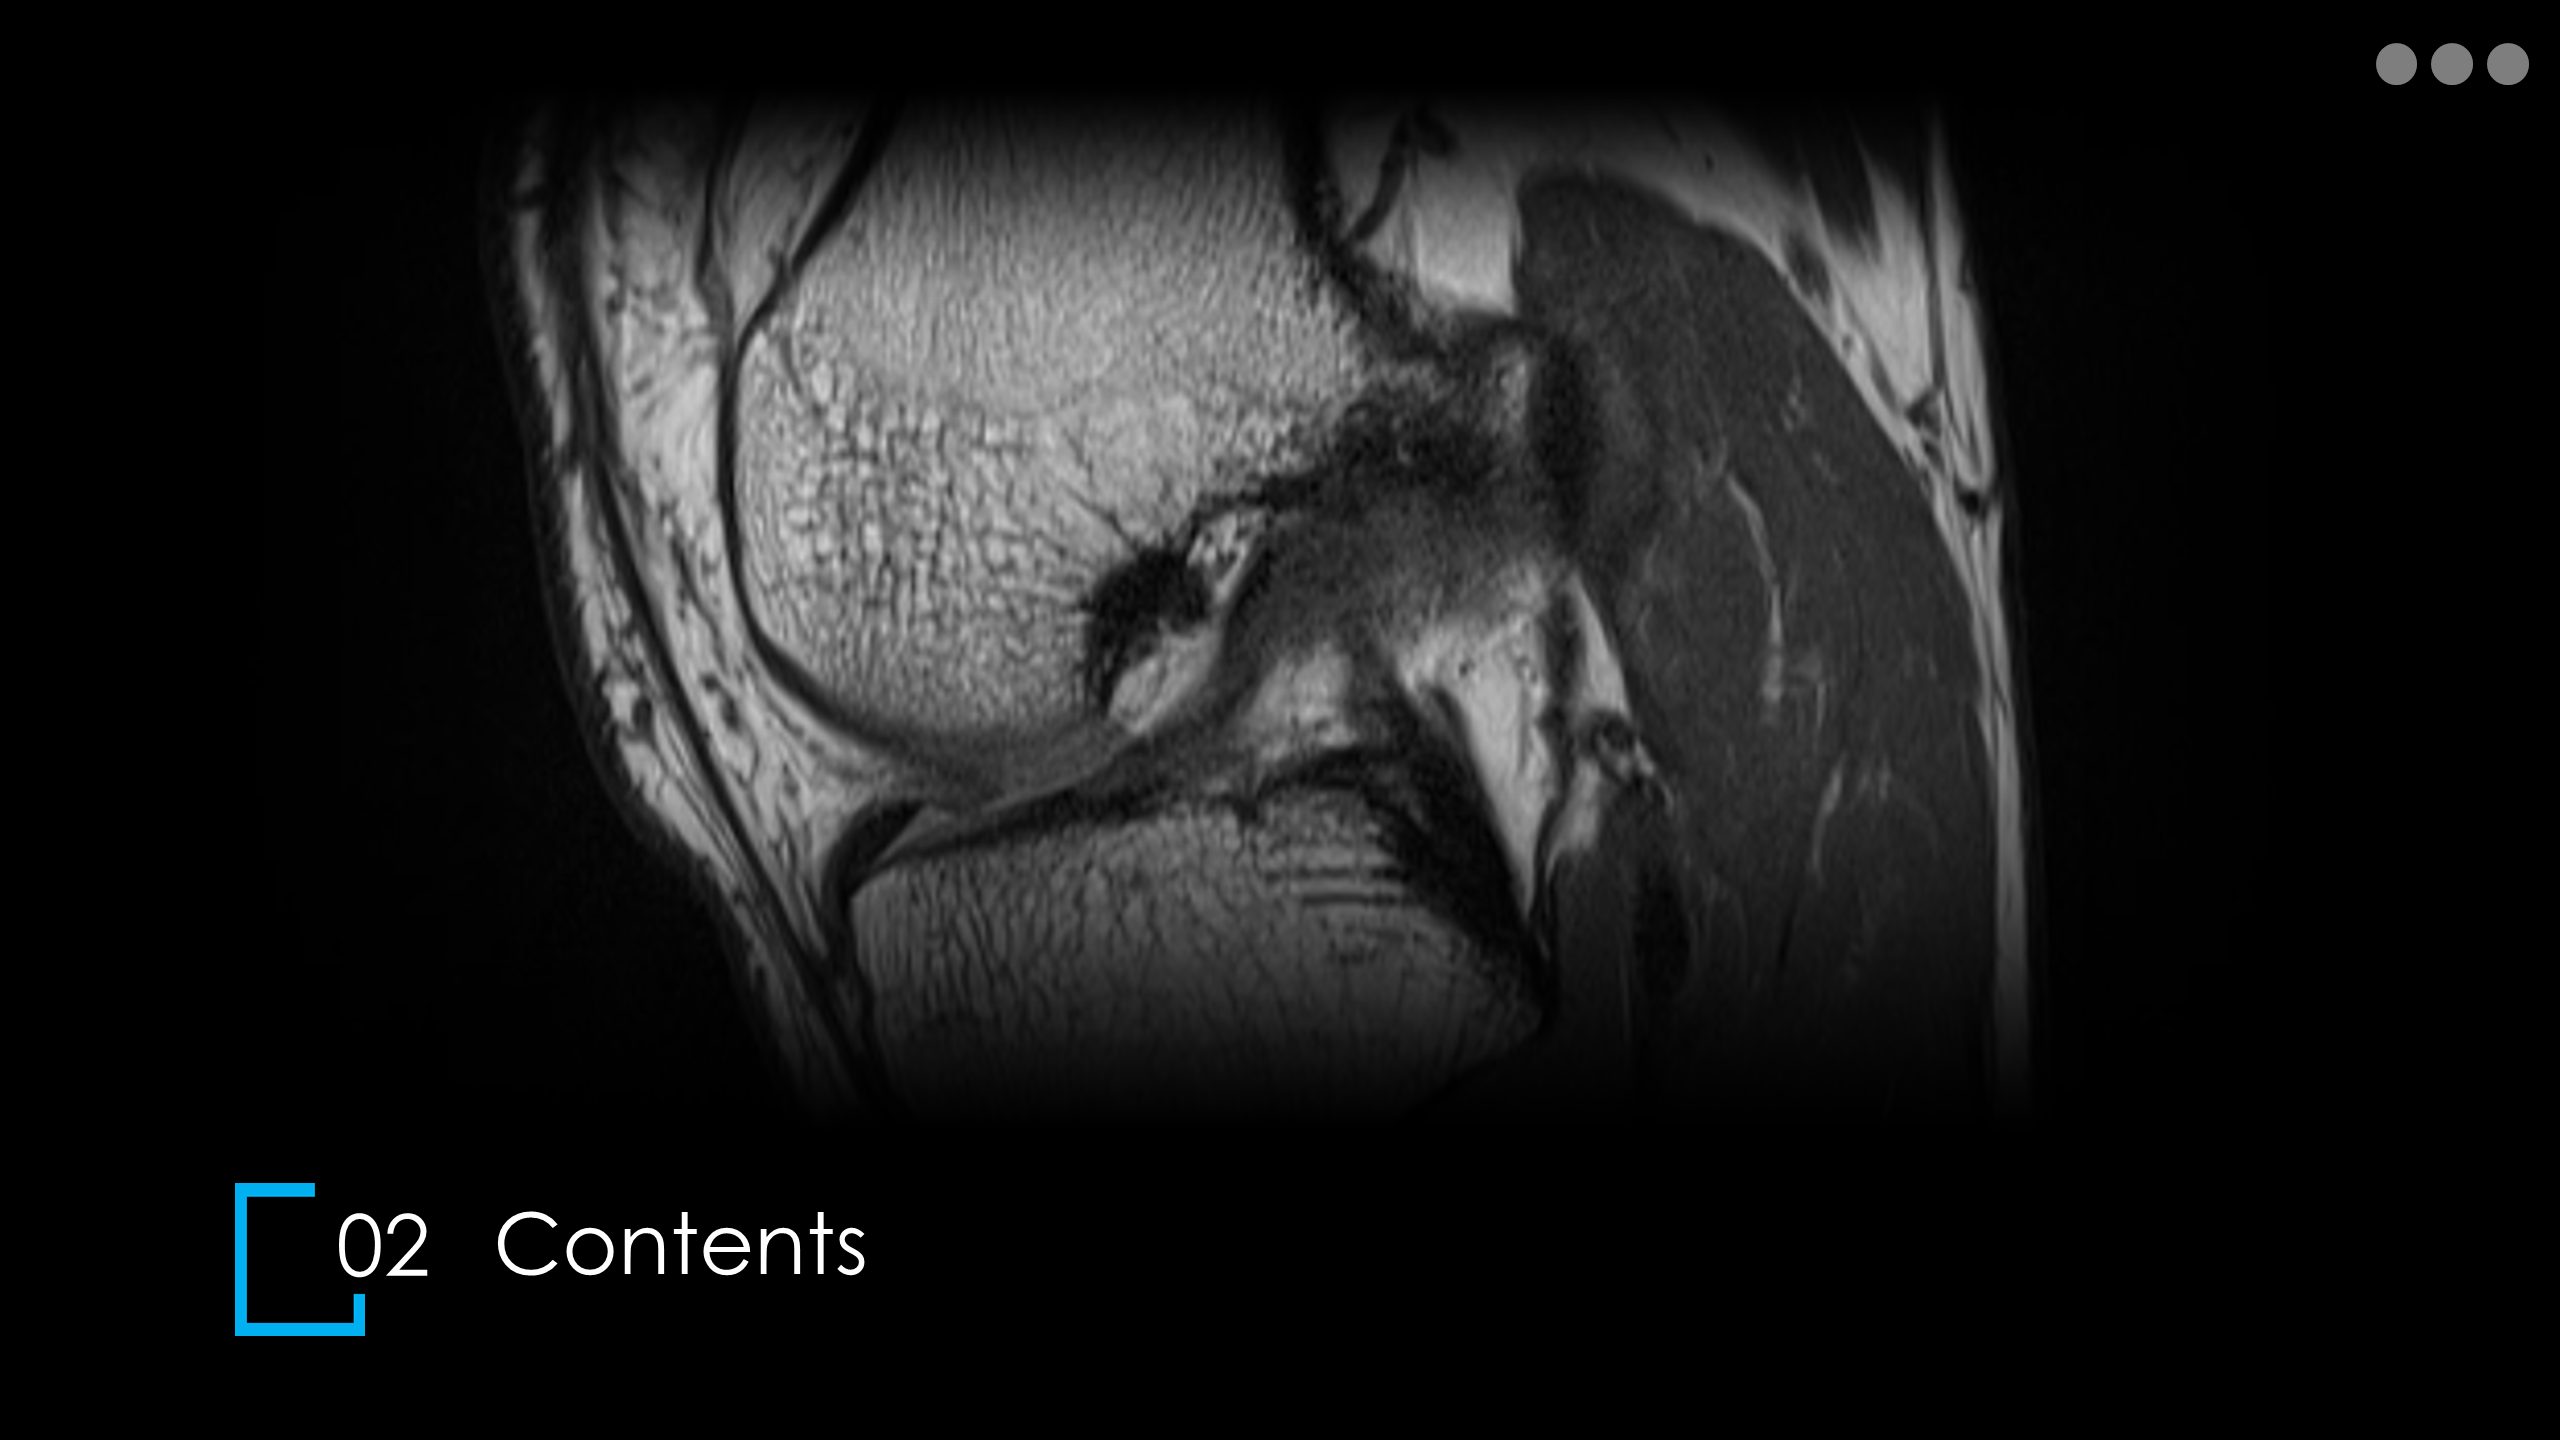

주제: The Knee MRI Approach

강사: 신민섭

아래의 Normal Knee MR Anatomy를 숙지하고 오셔야, 강의에 어려움이 없습니다.

Detailed Knee MRI Anatomy [대한연부조직한의학회].pdf